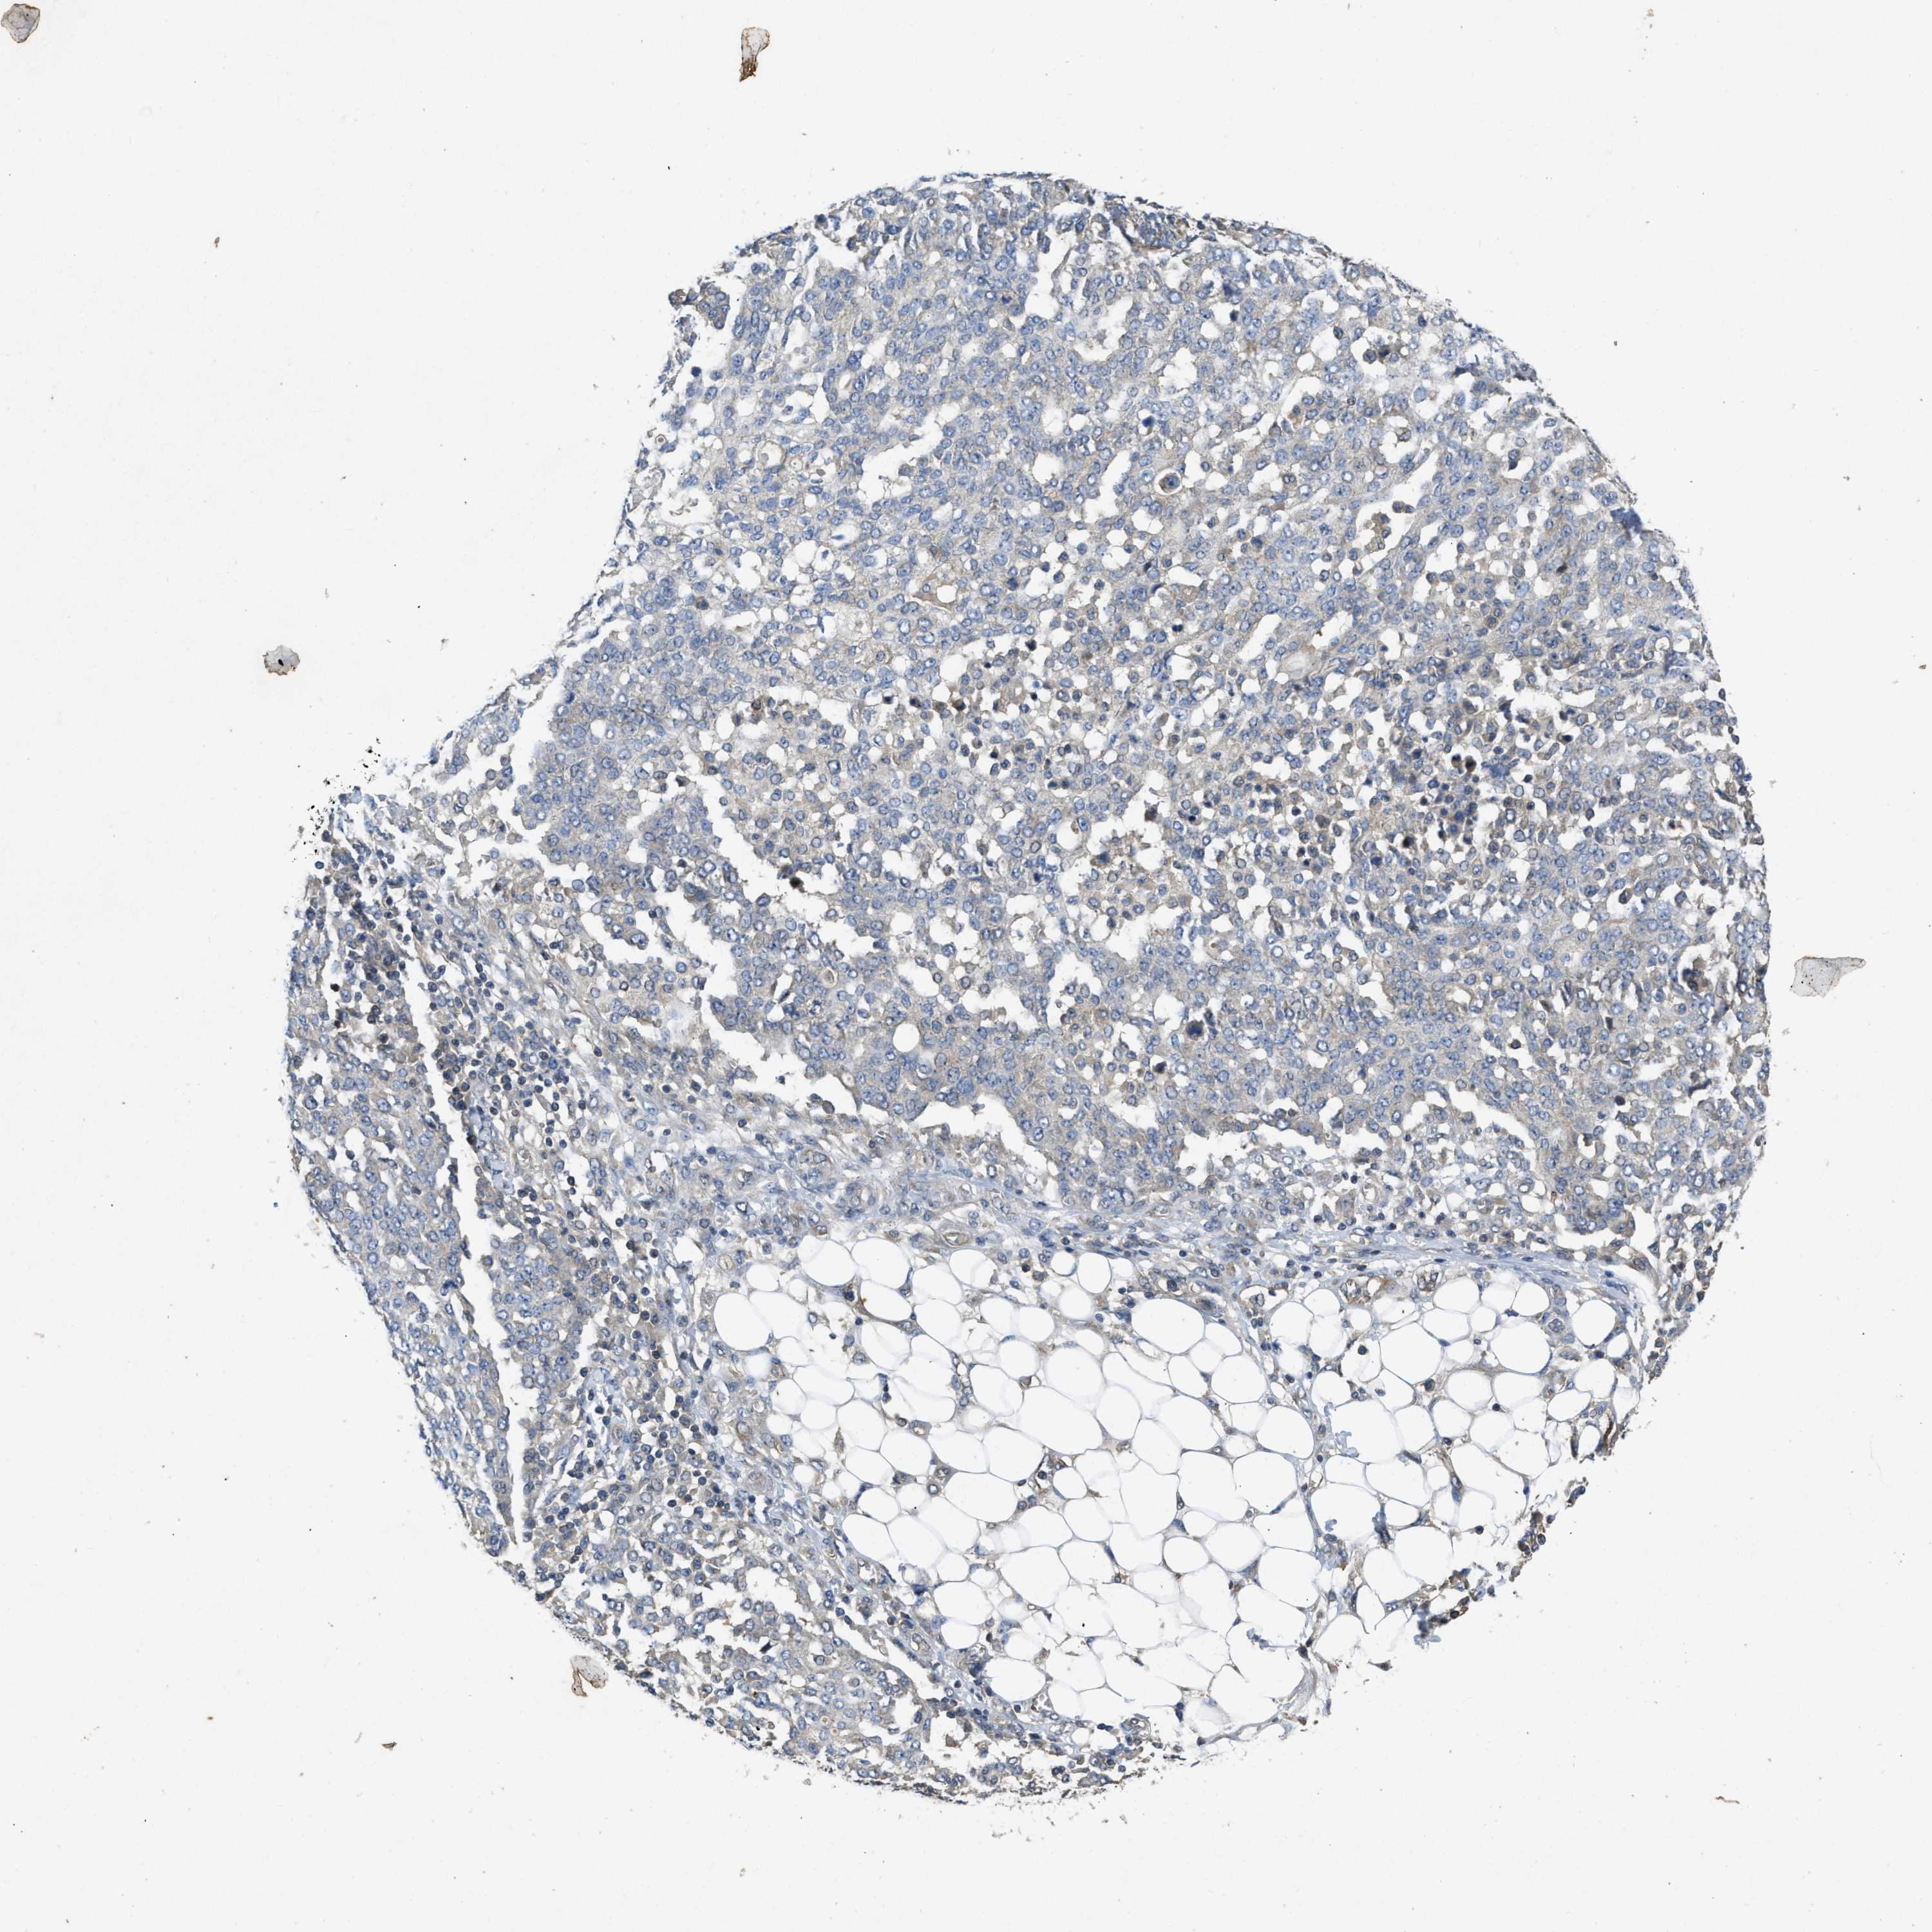

OVARIAN CANCER - Protein expressioni

A mouse-over function shows sample information and annotation data. Click on an image to view it in a full screen mode. Samples can be filtered based on level of antibody staining by selecting one or several of the following categories: high, medium, low and not detected. The assay and annotation is described here.

Note that samples used for immunohistochemistry by the Human Protein Atlas do not correspond to samples in the TCGA dataset.

Antibody stainingi

Antibody staining in the annotated cell types in the current human tissue is reported as not detected, low, medium, or high, based on conventional immunohistochemistry profiling in selected tissues. This score is based on the combination of the staining intensity and fraction of stained cells.

Each image is clickable and will lead to virtual microscopy that enables deeper exploration of all samples and also displays staining intensity scores, fraction scores and subcellular localization as well as patient and tissue information for each sample.

Antibody HPA012778

Antibody CAB018581

Cystadenocarcinoma, serous, NOS

Carcinoma, endometroid

Cystadenocarcinoma, mucinous, NOS

Carcinoma, NOS